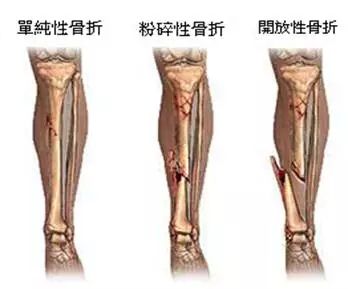

1、外伤骨头——粗看X光片、细看CT

0.webp (3).jpg

各种外伤,如果怀疑伤到了骨头,优先选择X光照片,检查结果快速易得。若要进一步观察,可以选择CT。超声、核磁对于骨皮髓质等看不大清,一般不选择。